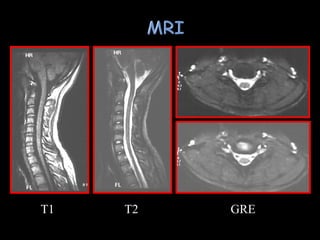

 Invaluable forassessing cord and soft tissues  R/O associated disc herniation ( facet dislocations)  Hemorrhage vs edema in soft tissues ????  Ligamentous tears and facet capsule disruptions visualized with fat suppression  May allow prognostic assessment of final motor function › Intrasubstance hematoma